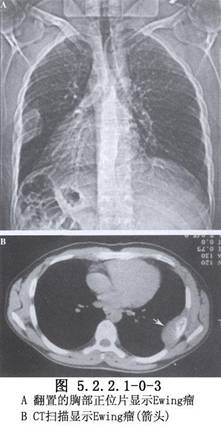

除病史及體格檢查外,還要攝胸部X線片,斷層攝影等必要的檢查。胸壁軟組織腫瘤X線片的特點爲陰影密度不高。切線位片瘤體中心位於側胸壁,瘤體與胸壁成鈍角。骨良性腫瘤一般爲圓形、橢圓形,骨皮質無斷裂。骨軟骨瘤常見在肋骨骨髓區內,頂部呈圓形或菜花狀,境界銳利,有不規則鈣化軟骨帽,瘤內有點狀鈣化。軟骨瘤常發生在肋骨與肋軟骨交界處,腫瘤有分葉,受累骨膨脹,骨皮質變薄,內有點狀鈣化,難與軟骨肉瘤鑑別。骨纖維結構不良,常發生在後側肋骨,始自嬰幼兒期,常到青壯年才發現,病竈呈侷限性膨大,骨皮質變薄,病變區呈磨玻璃樣變。肋骨骨鉅細胞瘤有皁泡狀透亮區,骨皮質薄如蛋殼。惡性腫瘤X線所見,主要爲侵蝕性骨破壞,呈篩孔樣、蟲蝕樣,可見溶骨或成骨性改變,邊緣較毛糙,骨皮質缺損、中斷或病理性骨折。軟骨肉瘤起自骨髓部分,呈分葉狀腫塊,邊緣不清,內有點狀或斑狀鈣化竈。骨肉瘤X線表現分爲溶骨型、成骨型及混合型3種。成骨型有放射狀排列的新生針狀骨小梁,邊界不清。Ewing肉瘤佔原發性胸壁骨腫瘤的12%,X線片見骨呈斑片狀破壞,含有溶骨和增生區,骨膜增生呈層狀,稱“蔥皮”樣改變。MRI可將腫瘤與血管區別,應採用不同平面瞭解腫瘤情況。活檢是診斷的可靠方法,應注意惡性腫瘤常有良性部分,多部位、足夠組織取材是正確診斷的關鍵。胸壁腫瘤的診斷十分重要,它決定治療方法的選擇(圖5.2.2.1-0-1~5.2.2.1-0-5)。